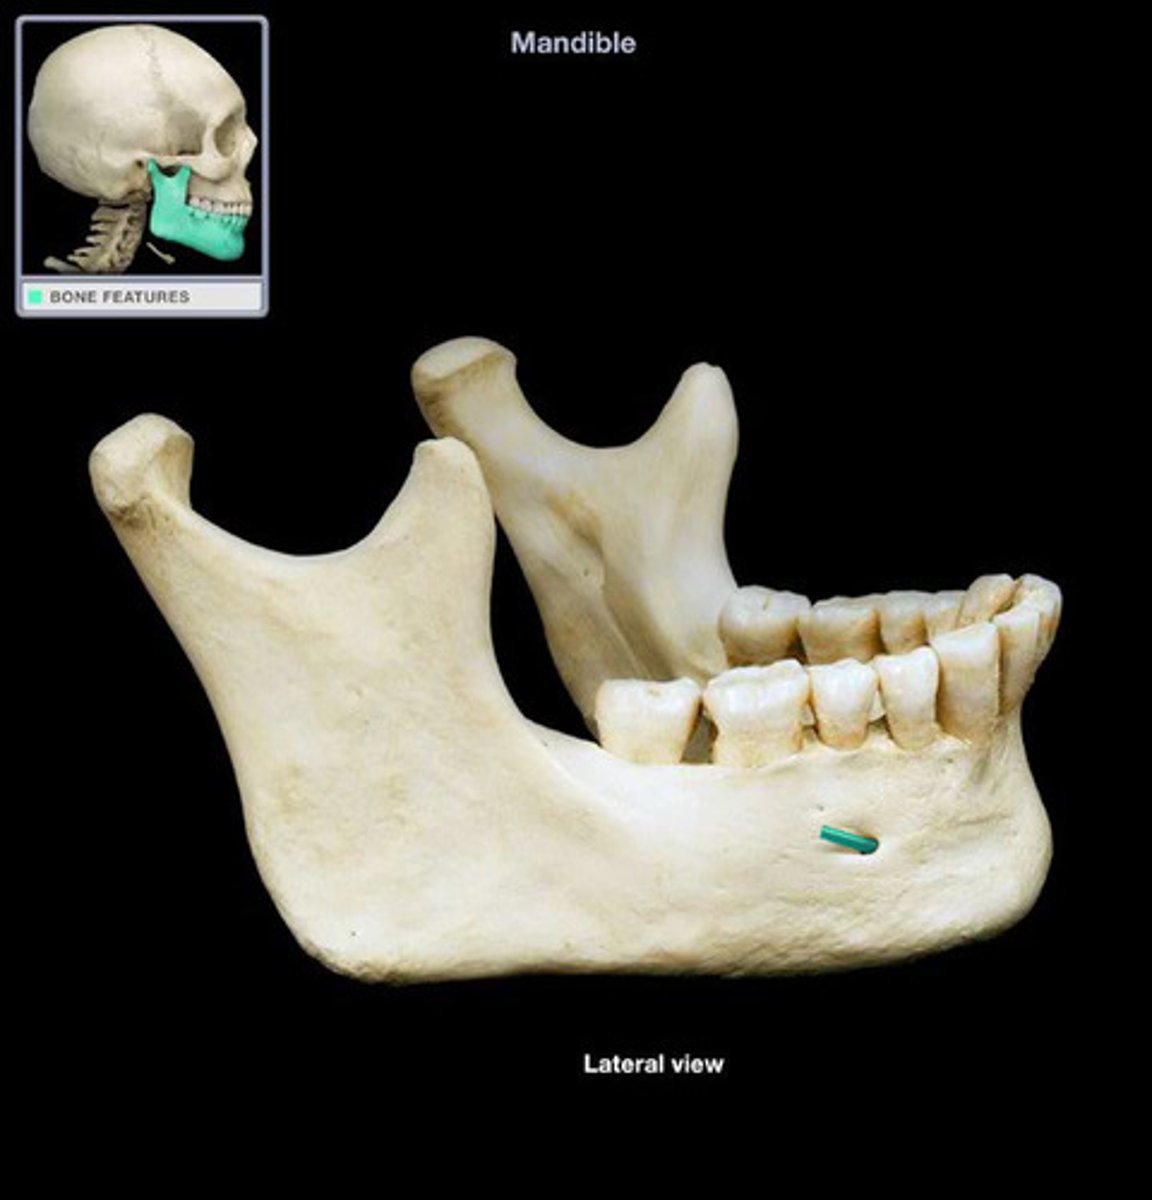

The horizontal section known as the body and two vertical sections known as the rami.

What are the two main sections of the mandible?

mental foramen

- small opening in the body where the mandibular passes through

what is this